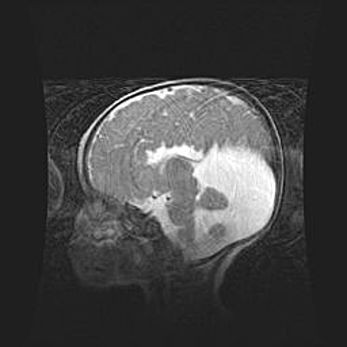

Множественные кисты обоих полушарий головного мозга, наибольшая из них в правой затылочной области. Ассиметричная атрофическая гидроцефалия.

Возраст: 7 месяцев

Вес: 5660 г

Пол: мужской

Окружность головы: 41,5 см

Срок гестации: 28-29 недель

Кисты головного мозга развиваются в результате многоочаговых некрозов вещества мозга и возникают вследствие перенесенной перинатальной инфекции, менингитов, энцефалитов, асфиксии, родовой травмы, расстройств мозгового кровообращения различного генеза. Образованию кист в веществе головного мозга плодов и новорожденных способствуют такие факторы, как высокое содержание в нем воды, недостаточная (или отсутствие) миелинизация и слабая астроглиальная реакция на повреждение.

Кисты могут сочетаться с гидроцефалией и другими поражениями головного мозга.